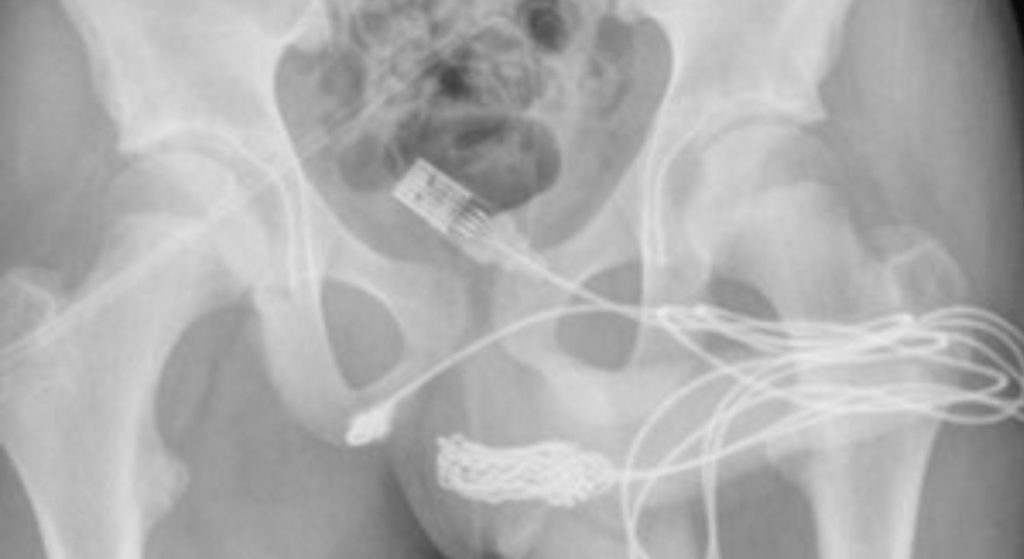

Las radiografías posteriores revelaron que había un verdadero enredo de cable dentro del adolescente. Por ello, los cirujanos hicieron una incisión en la región entre sus genitales y el ano para sacarlo. Primero tiraron del extremo enrollado a través del agujero, cortándolo libre del resto del cable antes de quitar los trozos restantes, literalmente tirando del enchufe.